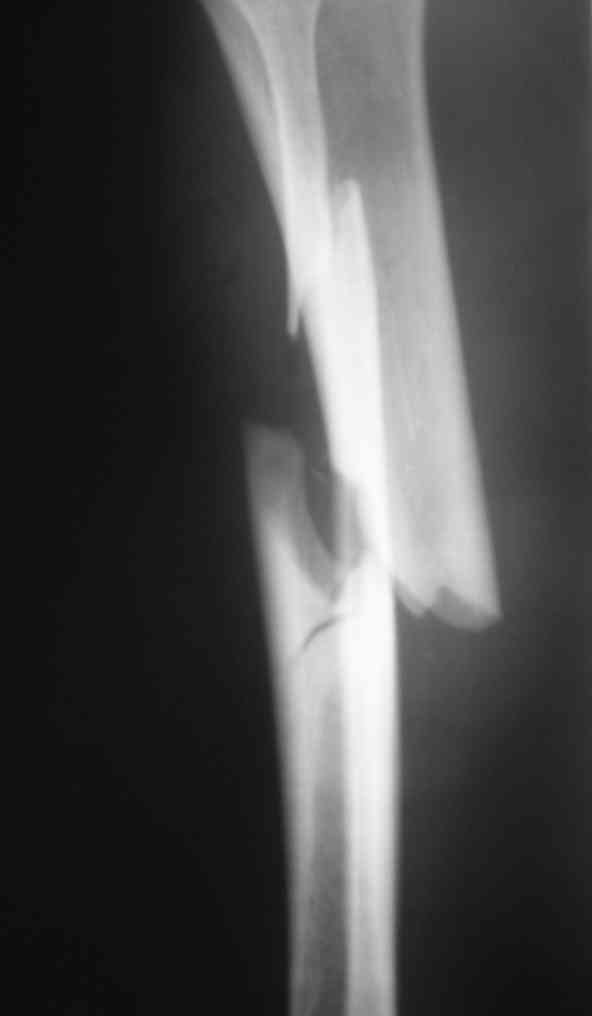

Дорогой Александр. Имею скромный опыт использования системы Fixion при переломах плеча, бедра и тибии. Всего 18 наблюдений с сентября 2006 г. Результаты отличные. Гвоздь индивидуален для каждого медуллярного канала. Легко имплантируется как в узкий, так и в деформированный канал. Это позволяет применять метод интрамедулярного остеосинтеза без ненужных потерь времени операции, флюороскопии и реально снижает крвопотерю и операционный риск. Удаление происходит без проблем. Особенно интересны больные с ипсилатеральными переломами бедра и голени.

В отношении ранней нагрузки при спиральных переломах лучше не торопиться. По данному случаю необходимо достигнуть исчезновения щели между штифтом и внутреним кортексом по Rg. А так картинка прекрасная - и длина сегмента и репозиция. Можно поздравить, коллега!

Да, спасибо за интересные иллюстрации. Получилось очень симпатично. На большеберцовой кости непременно надо было винты? Там же был торцовый упор, перелом в средней трети?